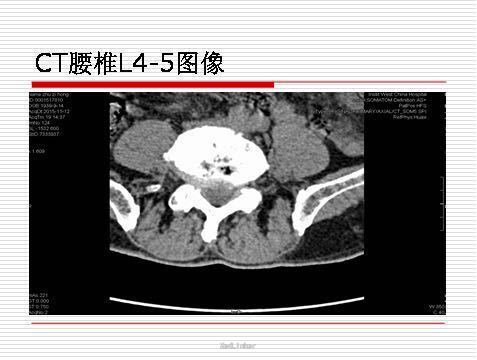

查体:患者神志清,跛行步入病房,脊柱四肢无畸形,腰椎前屈侧弯及旋转后伸不受限,四肢活动不受限。左下肢直腿抬高试验(-),屈颈试验(-),仰卧挺腹试验可疑(+),4字试验(-),右下肢正常。左大小腿正常,双下肢肌力正常,活动无障碍,左足小趾无压痛,无红肿及皮肤破损。L2-L4椎体棘突及椎间隙压痛叩击痛(-),椎旁肌肉压痛(+),加重时VAS评分5-6分,缓解时4-5分。 辅查:数字化X光腰椎功能位摄影 ---L5及L2稍显向后滑,脱腰椎骨质增生及骨质疏松。 腰椎CT ---L2-S1椎间盘轻微膨出。 L2-L3椎体轻度失稳。 腰椎及骨盆MRI---L2-S1椎间盘膨出,L2及L3椎体轻度失稳,老年性骨质疏松治疗,双侧骶髂关节退行性变 下肢肌电图----双侧下肢足周围神经源性损害

讨论:行CT引导下左侧S1神经阻滞?